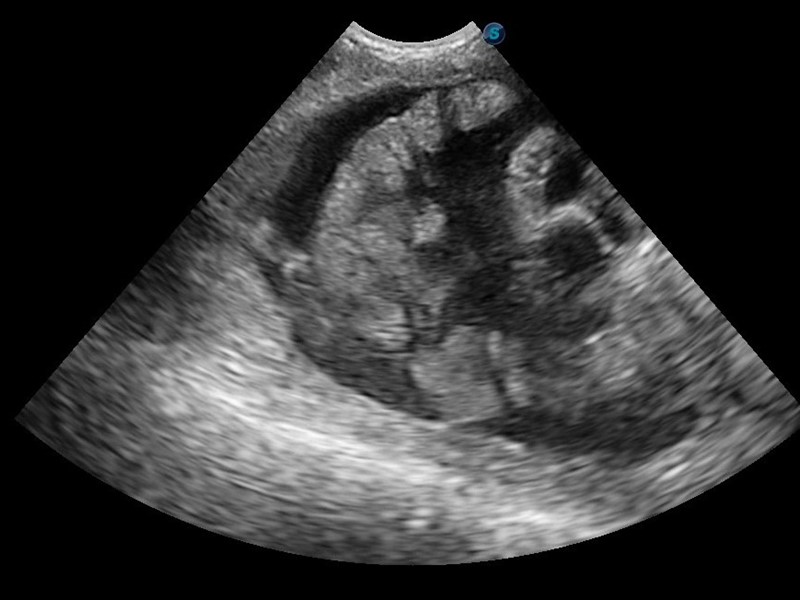

- POCUS for the Thorax - A lines, Glide sign, B lines, DH, CTS, PCS

- Pregnancy/pyometra identification

- Liver, Spleen, RK, LK, GI - related to emergencies